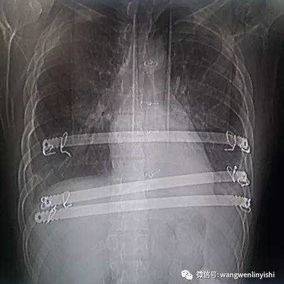

First, two 3 cm incisions were made on each side of the chest wall, followed by a 2 cm incision along the old surgical scar in the middle of the chest wall. Two bars were then placed on the protruding bone structures of the chest wall to perform the Wenlin procedure. Since the anterior chest wall is a rigid whole, correcting and pressing down the protrusion in the upper chest often causes a secondary depression below it. To address this, a third bar was inserted into the chest cavity to perform the Wung procedure, thereby elevating the depressed areas. Ultimately, the patient’s chest wall deformity was corrected, and the surgery achieved a satisfactory outcome.

In this case, the patient presented with a severe protruding chest wall accompanied by a slight depression. To achieve a better correction, the Wung procedure was performed subsequent to the Wenlin procedure, so that the concave deformity can be corrected as well.